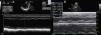

On admission he was apyretic, with pulse 190 bpm, respiratory rate 70–80 breaths per minute and oxygen saturation 95% in room air. His body weight was 6 kg (50th percentile). Physical examination revealed an infant of normal appearance but irritable and in respiratory distress. He was tachycardic, with an S3/S4 gallop rhythm. There were moist rales in the lung fields and chest wall retraction. The abdominal exam revealed hepatomegaly. The extremities displayed cyanosis and poor perfusion, with no edema. The chest X-ray showed cardiomegaly (cardiothoracic ratio 0.8) with pulmonary congestion (Figure 1A). The echocardiogram revealed a markedly enlarged left ventricular (LV) cavity with hypokinetic ventricular wall motion. LV end-diastolic diameter was 45 mm, LV end-systolic diameter was 40 mm, and fractional shortening (FS) was 5%, with no structural abnormalities (Figure 2). Electrocardiography showed sinus tachycardia (heart rate 190 bpm), LV hypertrophy and normal QTc.

Decreased serum calcium levels remained an issue while in the intensive care unit, requiring calcium boluses and drips to improve levels, which led us to study the patient's phosphorus–calcium metabolism. Hormone levels that were changed included elevated parathyroid hormone (231.8 pg/ml, reference value: 12–80 pg/ml), decreased 25-hydroxyvitamin D (5.94 ng/ml, reference value 11–70 ng/ml) and decreased 1,25 (OH)2 vitamin D3 (18.57 pg/ml, reference value: 20.2–46.2 pg/ml). There were no metabolic disorders on amino acid and organic acid tests. Calcium and vitamin D deficiency was confirmed and replacement with calcium and alfacalcidol (0.05 μg/kg/day) was started. As the levels of serum calcium increased to normal, the patient showed rapid recovery of cardiac function, normalization of LV dimensions and function on echocardiogram (Figure 3) and reduction of cardiomegaly on chest X-ray (Figure 1B). As the infant improved clinically, he was weaned to oral captopril, furosemide, spironolactone and digoxin. He was discharged on the 25th hospital day and followed in the outpatient clinic, with calcium gluconate and calcitriol replacement.